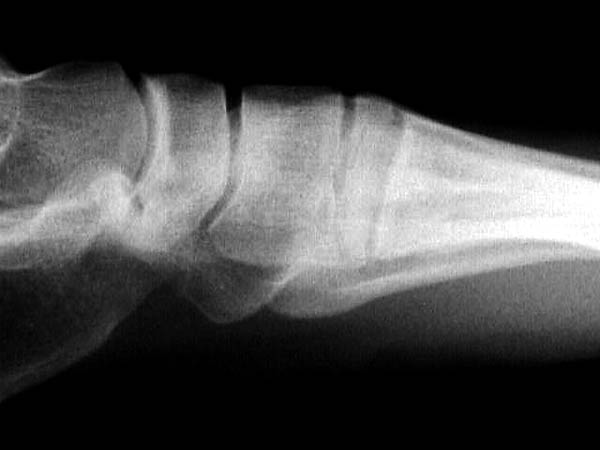

Здесь КТ и сравнительные снимки стопы под нагрузкой.

Диагностировано повреждение медиальной и латеральной колонны.

Если оперативное лечение - как и каким доступом?